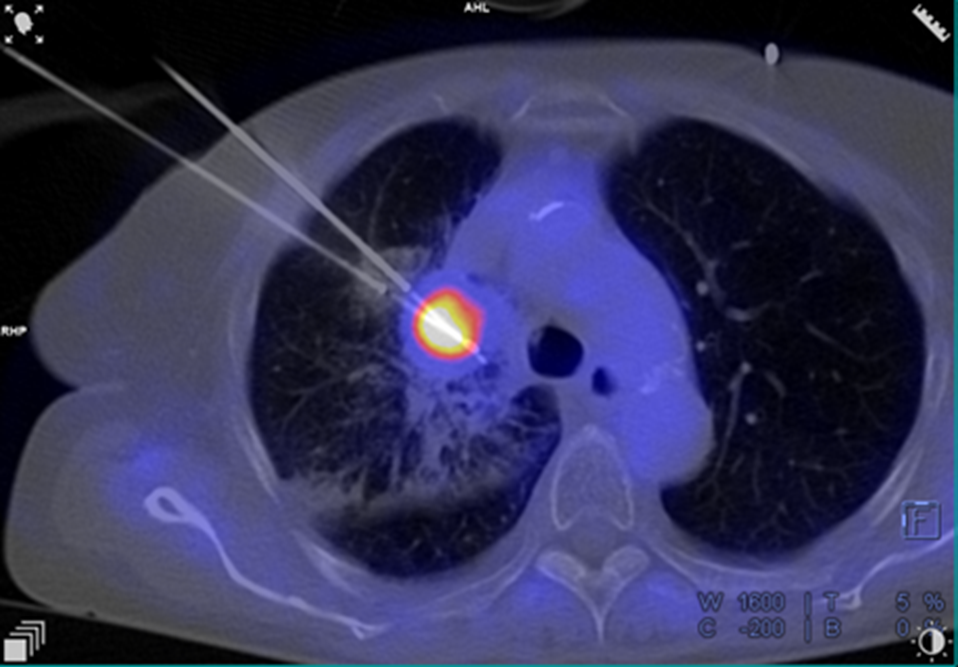

Een PET‑onderzoek toont de metabole activiteit van tumoren, terwijl een CT‑scan een zeer gedetailleerde anatomische weergave biedt. Door beide modaliteiten te combineren, beschikken radiologen over een nauwkeurige driedimensionale visualisatie van de tumor en de omliggende structuren.

Met de SOMATOM X.Ceed‑scanner (Siemens Healthineers) en de interventionele navigatiesoftware MyNeedleGuide is deze beeldfusie in realtime beschikbaar in de interventieruimte. Dat verhoogt de nauwkeurigheid van de naaldgeleiding aanzienlijk, vooral bij letsels die op een klassieke CT moeilijk zichtbaar zijn of zich diep in het longweefsel bevinden.

De grootste uitdaging bestond erin twee cryo‑ablatienaalden uiterst nauwkeurig te positioneren, om het tumoraal weefsel maximaal te vernietigen zonder schade aan de gezonde omliggende structuren aan te brengen.

Dankzij de gefuseerde beeldvorming en de continue monitoring tijdens de volledige procedure kon het team een precisie op millimeterniveau bereiken, wat leidde tot een optimale synergie tussen de manipulatie van de naalden en een maximale bescherming van het gezonde weefsel.